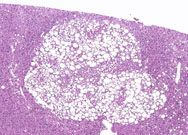

A vacuolated focus of cellular alteration comprised of a sharply demarcated collection of hepatocytes containing clear spaces. Some pathologists diagnosis this type of lesion as focal fatty change.